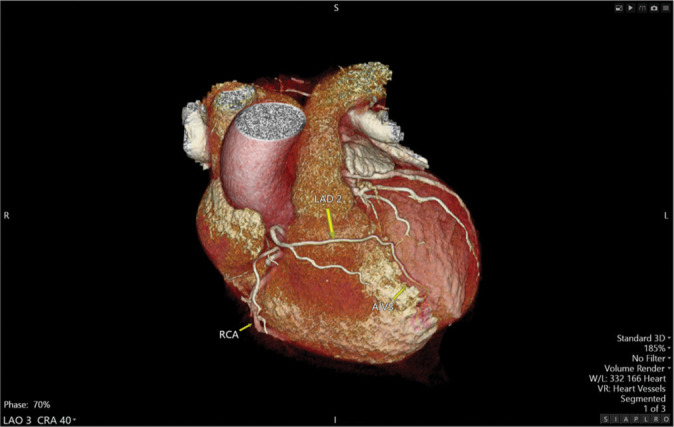

Dual left anterior descending (LAD) coronary artery is a rare anatomical variant with significant clinical implications. Recognizing this variant is crucial for accurate diagnosis and effective management, particularly in the context of revascularization strategies. We present a 71-year-old male with a history of dyspnea on exertion with baseline wall motion abnormality on a transthoracic stress echocardiography irreversible after exercise. Coronary computed tomography angiography revealed a dual LAD system: The left short LAD (LAD1) originating from the left main coronary artery and the right LAD (LAD2) arising separately from the right coronary cusp, distinct from the right coronary artery ostium. Having different origins and courses, both LADs supply the LAD territory. Our case is notable for two main reasons: The rarity of this particular type of dual LAD anatomy and the unique course of the LAD2, which, to our knowledge, has not been described in any previous case report. Although rare, dual LAD coronary artery should be considered in patients with atypical short LAD. Comprehensive imaging and a thorough understanding of coronary artery variants are essential for accurate diagnosis and effective management.

Abstract Image